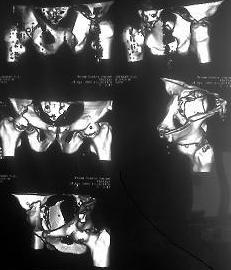

Re: Перелом вертлужных впадин

Извините, пробую еще раз